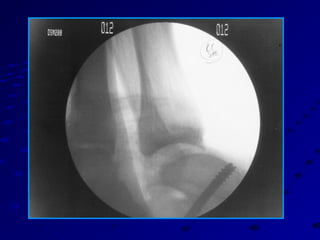

ArthroscopyArthroscopy

MRI is extremely important to R/OMRI is extremely important to R/O

tendinous, extraarticular and intraosseoustendinous, extraarticular and intraosseous

lesions.lesions.

Stress testing under anesthesia with fluoroStress testing under anesthesia with fluoro

is accurate and helpfulis accurate and helpful

Arthroscopy best evaluates cartilageArthroscopy best evaluates cartilage

status, OCDs, loose bodies, anteriorstatus, OCDs, loose bodies, anterior

impingement lesionsimpingement lesions